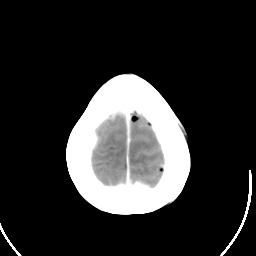

Metastatic bronchogenic carcinoma: Roentgen-ray CT (post-op) -- Slice #20

[Home][Help][Clinical] Slice 20